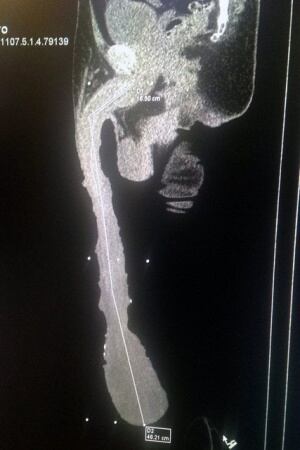

Algunos podrían creer que tener el pene más grande del mundo es lo mejor que le puede pasar a un hombre. Sin embargo, no se han imaginado lo terrible que puede llegar a tener un órgano de 48 centímetros y 900 gramos, y verse completamente discapacitado.

El mexicano Roberto Esquivel Cabrera es considerado el hombre con el pene más grande del mundo, quien según señaló Metro, no puede encontrar trabajo debido a su enorme tamaño. El hombre de 55 años aseguró que no puede usar uniforme como el resto de los trabajadores y que no puede ponerse de rodillas.

Asimismo, pese a que sus médicos le recomiendan operarse para tener una vida normal, Esquivel sufre de distintos dolores y dificultades para orinar. Al dormir tampoco puede hacerlo cómodamente y necesita poner una almohada especial para su pene.

Y los médicos de Esquivel confirman sus teorías, ya que su largo pene es prácticamente puro prepucio alargado. Debajo de ello, su pene realmente mide unos 17 centímetros.